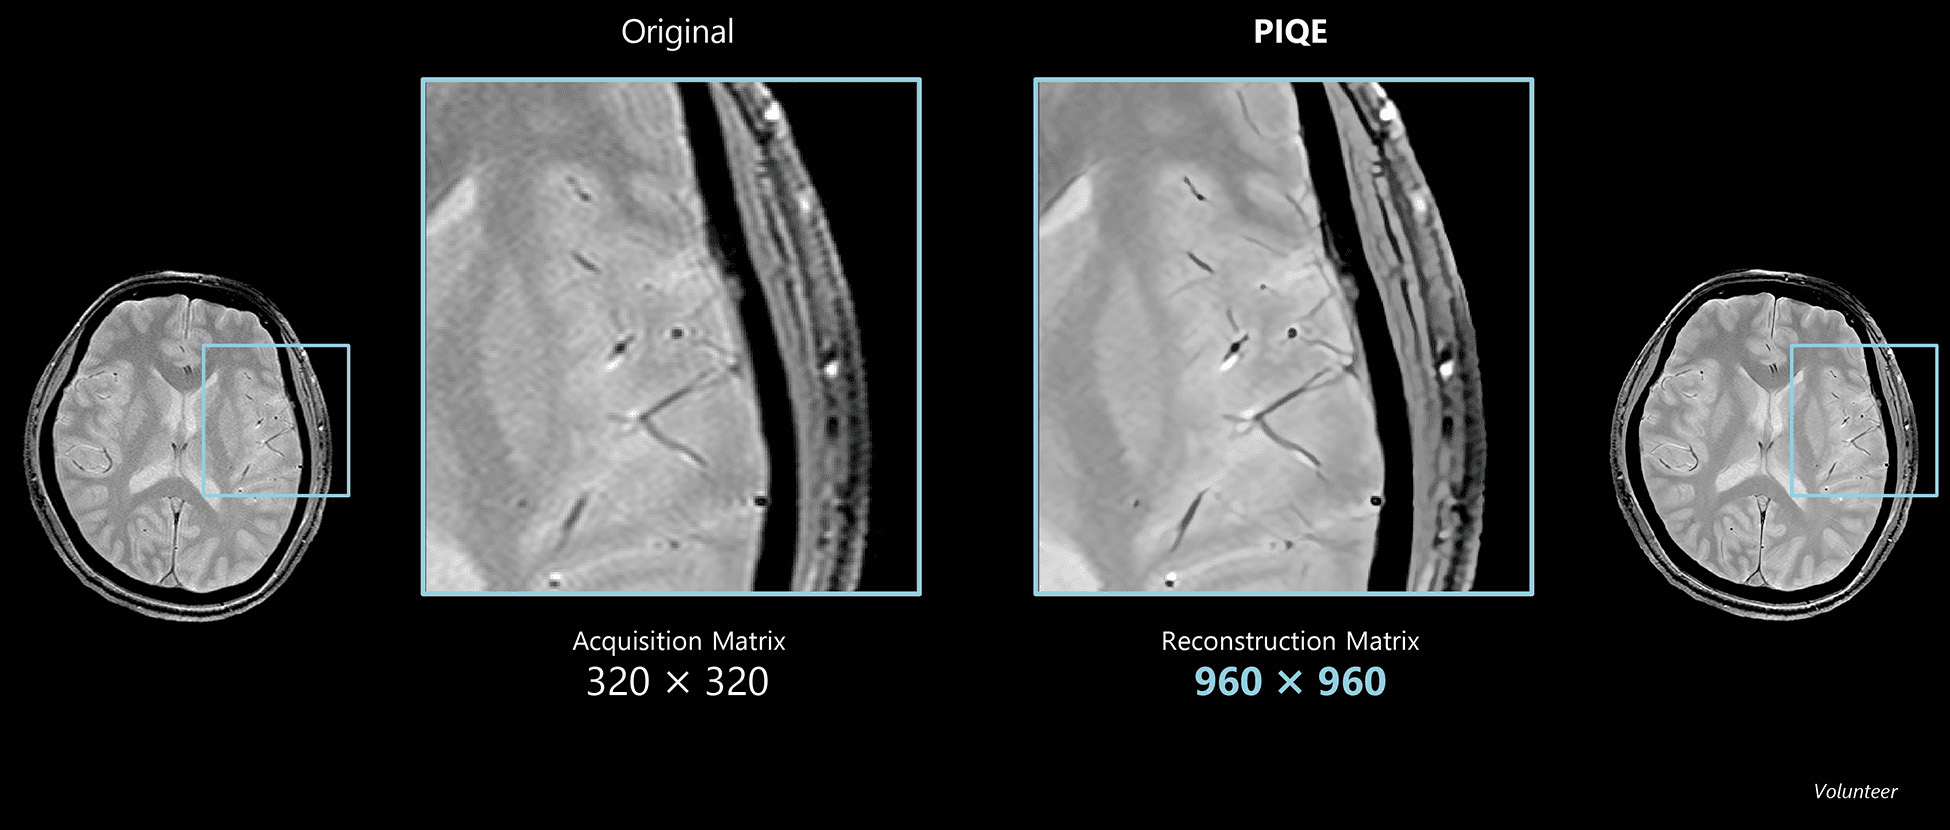

Brain

Vantage Galan 3T

Axi T2w for Brain

As this case is acquired with a 3T system, increasing the matrix over 512 × 512 will result in poor SNR and reduced contrast.

PIQE was applied after reducing the matrix to improve SNR and further shorten the scanning time.

As a result, scan time was reduced by 52% while still achieving high resolution.

Conventional

Axial T2w, Acquisition matrix 384 x 384, 0.58 x 0.58 mm resolution, 4 mm, 2:42

Conventional

Axial T2w, Acquisition matrix 320 x 320, 0.7 x 0.7 mm resolution, 4 mm, 1:18

PIQE

Axial T2w, Reconstruction matrix 960 x 960, 0.46 x 0.46 mm resolution, 4 mm, 1:18

Courtesy of Rothschild Foundation Hospital, France

Deep Learning Reconstruction for MR: PIQE

Precise IQ Engine (PIQE)

Accelerate high resolution imaging

PIQE accelerates scanning by reducing the acquisition matrix and enables acquisition of higher resolution images.

Actual scan time and scan time reductions shown throughout this gallery may vary by case.